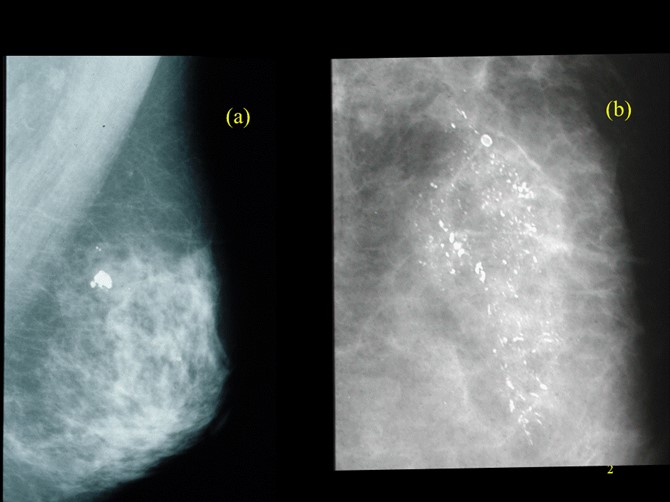

【112-1 醫學(五) 第42題】如圖mammogram所示,下列敘述何者錯誤?

本題考驗乳房攝影(mammogram)鈣化點的判讀與BI-RADS分類,以及後續處理原則。圖片(a)顯示良性鈣化,圖片(b)顯示惡性可疑的微鈣化。解題核心在於區分良惡性鈣化點的影像特徵,並理解不同BI-RADS分類的建議處置,特別是當超音波無法定位病灶時的處理方式。